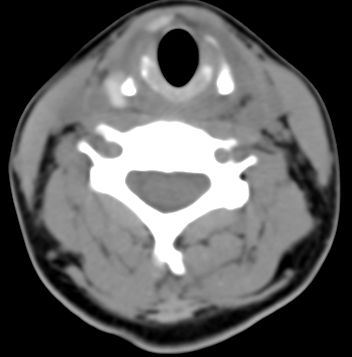

标题: CT9717:F、30Y、颈部左侧包块半年,压痛.患者拒绝作增强。 [打印本页]

标题: CT9717:F、30Y、颈部左侧包块半年,压痛.患者拒绝作增强。

请各位老师帮忙看看左侧甲状腺病灶!

左侧甲状腺见一低密度灶,考虑甲状腺占位。(腺瘤?)

甲状腺弥漫增大,以左叶明显,内见不均匀低密度影,边缘模糊欠清,周围脂肪间隙模糊。

结合病史:考虑亚急性甲状腺炎可能性大。(不知道病人有没有检测tsh t3 t4)

左侧甲状腺及甲状腺狭部弥漫性增大,边缘模糊,未见明确界线.考虑甲状腺炎可能性大.

左侧甲状腺弥满性增大,其内密度均匀减低,气管无受压。周围结构清晰。考虑甲状腺炎可能性大。

甲状腺弥漫增大,以左叶明显,左侧内见不均匀低密度影,边缘模糊欠清,周围脂肪间隙模糊。